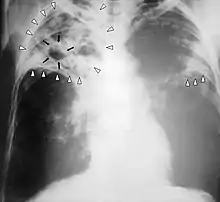

အဆုတ်တီဘီ

တီဘီရောဂါစတင်ဖြစ်ပွားပါက အဆုတ်တွင်ပါဖြစ်ပွားမှုမှာ ၉၀% ခန့်ရှိသည်။[11][12] ရောဂါလက္ခဏာများတွင် ရင်ဘတ်နာခြင်းနှင့် ရက်ရှည်ချောင်းဆိုးပြီး သလိပ်ထွက်ခြင်းတို့ ပါဝင်သည်။ ၂၅% ခန့်မှာ ရောဂါလက္ခဏာမပြတတ်ပေ။[11] ရံဖန်ရံခါ ချောင်းဆိုးသွေးပါခြင်းများ ဖြစ်တတ်ပြီး၊ ရှားပါးဖြစ်စဉ်အချို့တွင် အဆုတ်သွေးလွှတ်ကြောကို ကူးစက်ထိပါးစေကာ အပြင်းအထန်သွေးယိုစီးခြင်းကို ဖြစ်ပေါ်စေသည်။[9][13] တီဘီရောဂါသည် နာတာရှည်ရောဂါတစ်ခုဖြစ်လာကာ အဆုတ်၏ အပေါ်ခြမ်းတွင် ဒဏ်ရာဒဏ်ချက်ကြီးကြီးမားမားရစေနိုင်သည်။ အဆုတ်အပေါ်ဖက်ပိုင်းသည် အောက်ပိုင်းထက် တီဘီရောဂါကြောင့် ပိုထိခိုက်စေပြီး [9] အကြောင်းရင်းကို တိတိကျကျမသိရသေးပေ။[1]